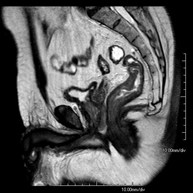

Prova diagnòstica no invasiva que consisteix en l'obtenció d'imatges d'alta definició anatòmica de l'abdomen mitjançant l'ús d'un camp electromagnètic i ones de ràdio (amb un emissor i un receptor). No utilitza radiació ionitzant. En aquesta exploració s'inclouen el fetge, el pàncrees, la melsa, la via biliar, la vesícula biliar, les glàndules suprarenals, els ronyons, l'aorta abdominal, la vena cava inferior, l'estómac, el duodè, etc. En alguns casos caldrà emprar contrast paramagnètic (Gadolini) per caracteritzar les lesions. - RM Pelvis femenina

Prova diagnòstica no invasiva que consisteix en l'obtenció d'imatges d'alta definició anatòmica de la pelvis mitjançant l'ús d'un camp electromagnètic i ones de ràdio (amb un emissor i un receptor). No utilitza radiació ionitzant. Es realitza per a l'estudi de patologies d'úter, d'ovari, de trompes i de vagina, ja siguin d'origen tumoral, inflamatori o vascular. També permet valorar les estructures adjacents localitzades a la pelvis i la identificació de les seves alteracions. De vegades és necessari l'ús de contrast intravenós (Gadolini) per caracteritzar les lesions. - RM Pelvis masculina